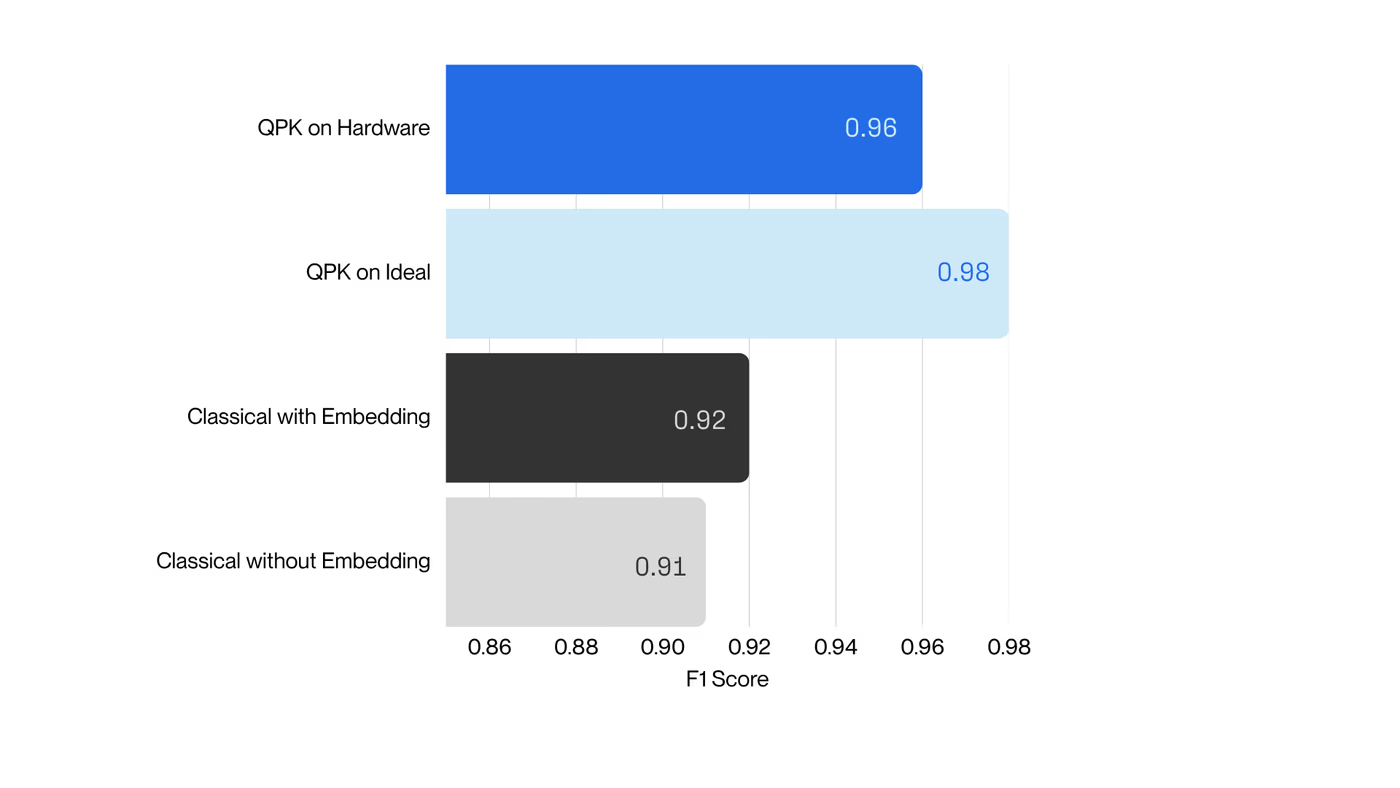

With R&D costs exceeding $2B per drug, pharma increasingly combines machine learning and computational chemistry to accelerate discovery. A powerful approach uses first-principles calculations to generate “quantum fingerprints”—physically grounded features that improve reactivity prediction. However, classical simulation methods scale poorly: they rely on approximations that are either too inaccurate to capture critical many-body effects or too expensive for practical screening.

Quantum computing offers a solution, but until now has been constrained by hardware noise, limiting usable circuit depth to a few hundred two-qubit gates. Haiqu, working with Capgemini, IBM, and GSK, broke this barrier by demonstrating one of the largest electronic-structure Hamiltonian simulations ever run on real quantum hardware for covalent drug warheads. Using advanced circuit compression and middleware execution, the team initially reduced circuit depth by 15.5× and further allowed end-to-end execution by running sub-circuits up to 371 gates.

Collectively, these results establish a scalable, hardware-realistic path for running Hamiltonian simulations on larger active spaces, while maintaining sufficient accuracy for molecular reactivity prediction.